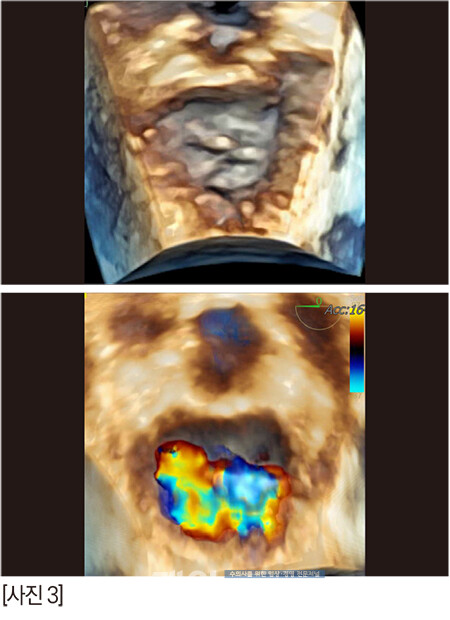

술자가 수술을 타이트하게 준비하고 각오를 하면 아이러니하게도 수술이 별일 없이 흘러간다. 마치 수혈 준비를 하고 수술을 하면 수혈할 일이 안 생긴달까[사진 7].

다행히 정답 zone에 안착했다.

[사진 8] P1-2 사이의 deep cleft like indentation 때문에 역류는 조금 남겠지만 술 전보다 나은 상황으로 만들고, 거기서 더 이상 진행만 안되면 충분히 괜찮다.매우 매우 걱정했지만 다행히 수술은 무사히 끝났고, 브이클램프를 close하는 시도도 한번으로 끝났다.

그렇다면 열 다섯살 반 짱아의 회복은 어땠을까?

수술 2시간 후의 짱아, 정말 대단하다!!!!! [사진 9] 잘 회복해서 3일차에 퇴원을 했지만 나이가 고령이어서 분명 크고 작은 문제들이 수술 2~3주 내에 지나갈 것 같았다.